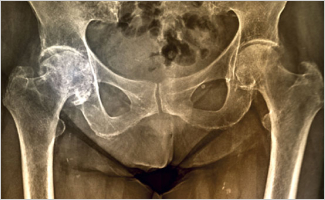

Radiographic Hip OA Increased, But Pain Decreased, After 10 Years

During a 10-year follow-up study of patients with hip pain, the prevalence of radiographic hip osteoarthritis (OA) increased steadily, but pain was reduced and function remained stable. These findings were published in Osteoarthritis.